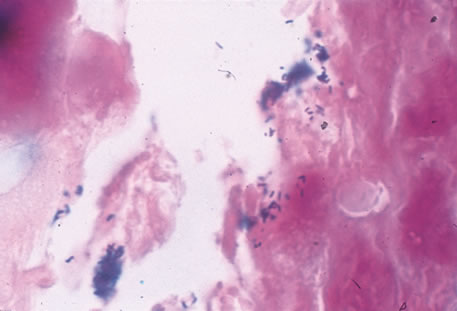

Any cell type may be infected, appearing larger than normal (cytomegalic) and demonstrating eosinophilic intranuclear “owl's eye” and smaller intracytoplasmic viral inclusion bodies, which are better seen with Giemsa or Papanicolaou's stains (Fig. 8). Histologic examination of tissue specimens, including bronchoalveolar lavage fluid and urine, may be useful for diagnosis.